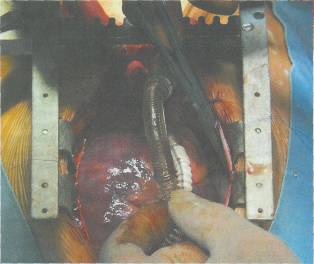

Yapay karaciğer oluşturmak, teknik açıdan oldukça güç. Poliüretan köpük iskelet kullanan bilim adamları yapay karaciğer oluşturabiliyorlar. Köpük içine yerleştirilen karaciğer hücreleri, mikrokümeler oluşturuyor. Elde edilen üç boyutlu yapay karaciğer vücut dışında 10 gün süreyle işlev görüyor. Karaciğer yetmezliği olan domuz ve farelere yerleştirilen bu yapay karaciğerler oldukça iyi sonuçlar verdi. Bilim adamları, deney aşamasındaki köpük karaciğerleri daha da geliştirerek, insanlarda kullanımı için çalışıyorlar.